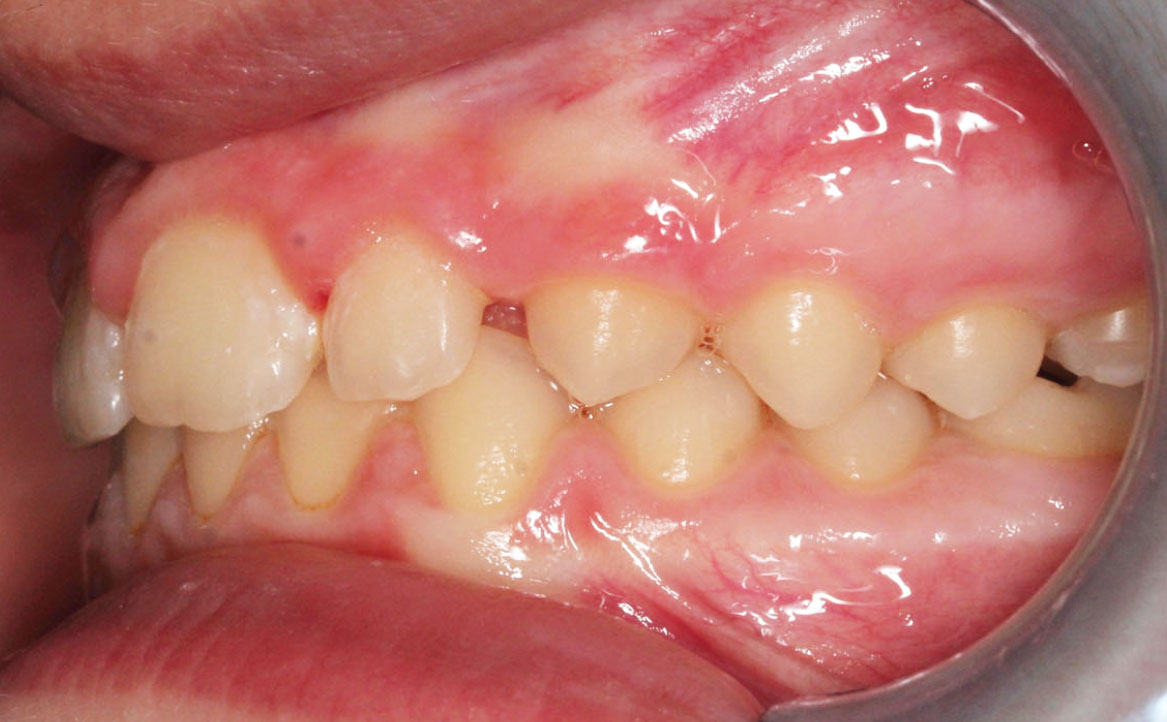

A livello intraorale sul piano sagittale è osservabile I classe molare destra e sinistra e classe canina non valutabile per mancanza degli elementi dentari durante la fase di permuta.

L’overjet e l’overbite sono entrambi ridotti in massima intercuspidazione. Trasversalmente il mascellare superiore è contratto (fig. 4-7).

Fig. 4A Foto intraorale in massima intercuspidazione.